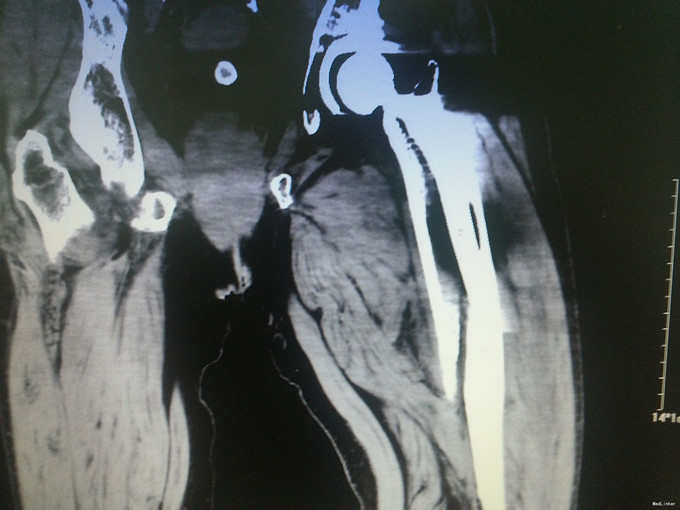

诊断:假体周围骨折(左股骨假体柄周围骨折);高血压病;脑梗死后遗症;陈旧性肺结核 治疗:手术治疗[左侧股骨假体取出术+左侧股骨假体周围骨折切开复位钢板钢缆内固定术(zimmer)+左侧股骨假体置入术(MP,Link)] 术中探查及处理:股骨大粗隆崩裂,骨折线自近端向远端延伸至股骨中段,呈螺旋形,骨折块粉碎,移位明显。骨折断端可见淤血块。顺利取出假体柄后,复位骨折块,予复位钳临时固定后,予钢板钢缆(zimmer)加压捆扎。待骨折固定牢靠后,按照髋关节置换流程逐步扩髓,最后选择25omm长的14号假体(MP,Link)安装,36mm标准颈股骨头复位。测试各方向活动良好,松紧度合适。

讨论: 一、诊断:结合患者既往史及影像学表现,不难诊断。结合术中探查,骨折线延伸到假体柄以远的位置,假体松动。因此该假体周围骨折按温哥华分型属于C型。 二、治疗:手术治疗首选。患者既往基础病较多,结合入院检查检验评估病情后,认为患者手术耐受性可,故建议手术治疗。患者家属态度积极。 三、经验: 1.术前详细评估很重要。我们予CT平扫详细评估骨折状况,准备了足够长的假体和骨折内固定装置。平片显示髋臼假体良好,故未行髋臼翻修。 2.患者既往长期服用阿司匹林,凝血功能偏差,且因中风欠活动导致骨质疏松,预计术中出血量较多,因此术前准备自体血回输器,并备同型红细胞悬液。保证了充足的血容量。且术后积极加强补液,患者术后未出血失血性休克的不良反应。 三、反思:人工关节翻修代价极大,不仅对术者的水平是大的挑战,对患者的身体及经济更是一种非常大的挑战。 1.该患者基础病多,身体偏差,再次手术对身体创伤极大,手术并发症风险极高。 2.关节翻修需要特殊的假体及内固定装置,手术花费也巨大,普通家庭很难承担。 3.翻修手术出血多,手术时间长,感染率远高于初次关节置换,住院时间长。 该患者中风史,手脚行动不利,于我院行初次全髋关节置换后回家疗养,不慎跌倒致假体周围骨折,跟我们没有做好宣教工作有一定关系。这个病例,让我们更加重视患者出院时防跌倒、防脱位等宣教工作。